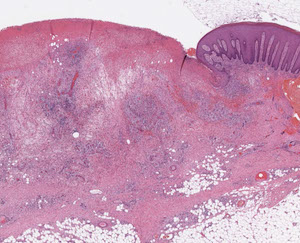

Porphyria cutanea tarda c festooning of the dermal papilla (protruding into the blister)

Porphyria cutanea tarda (PCT)

MCC porphyria in the states; assoc c Hep C and AIDS, EtOH, iron overload and possibly inherited deficiency of uroporphyrinogen decarboxylase (in heme synth), which are found in the liver

- get blisters in sun-exposed areas (back of hands)

Subepidermal pauci-inflammatory vesiculation; thick acral skin c compact orthokeratosis;

- Caterpillar bodies - compact hyaline material

- festooning of dermal papillae (protrude into blister)

- hyalinization of blood vessels

IHC: PAS can highlight deposition of perivascular hyaline

IF: IgM and C3 in vessels (absorbed by hyaline)